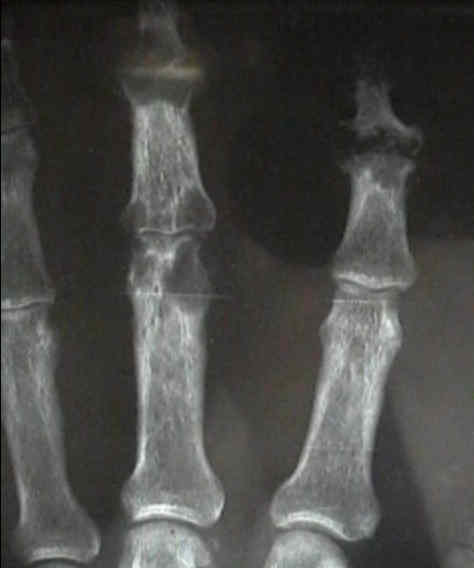

Radiographs

- in the hand look for oval periarticular erosions;

- multiple erosions will be distributed throughout the carpi and phalanges bilaterally;

- erosions have sclerotic borders and will often have overhanging edges;

- unlike classic RA, in early gout, hand and wrist joints will have preserved joint spaces and normal mineralization;

- example:

- case of histologically proven gout involving the proximal 5th metatarsal: